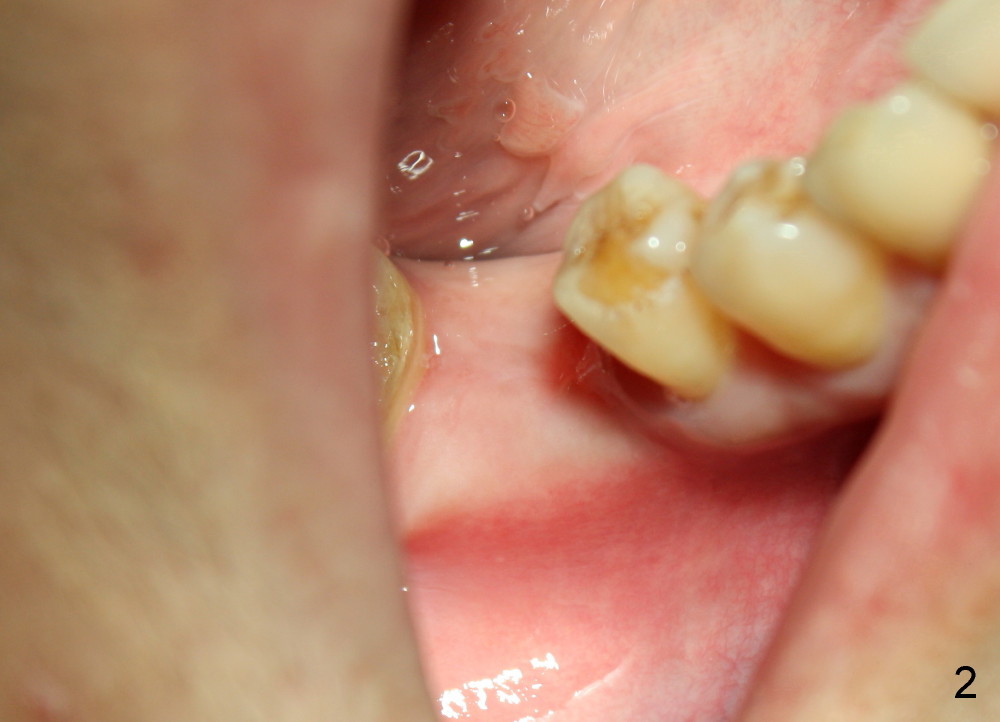

A 43-year-old lady presents to our office for implant 1 month post extraction. Treatment plan is to place a soft tissue level implant (1 stage). The surgery is finished as planned, but there is post-implant infection. The implant is removed with bone graft. Three months post implant removal, the socket heals (Fig.1) with wide ridge (Fig.2). Her oral hygiene remains not so pristine. To reduce the chance of infection, submerged implant is planned (2 stages). Oral Amoxicillin is taken preop.